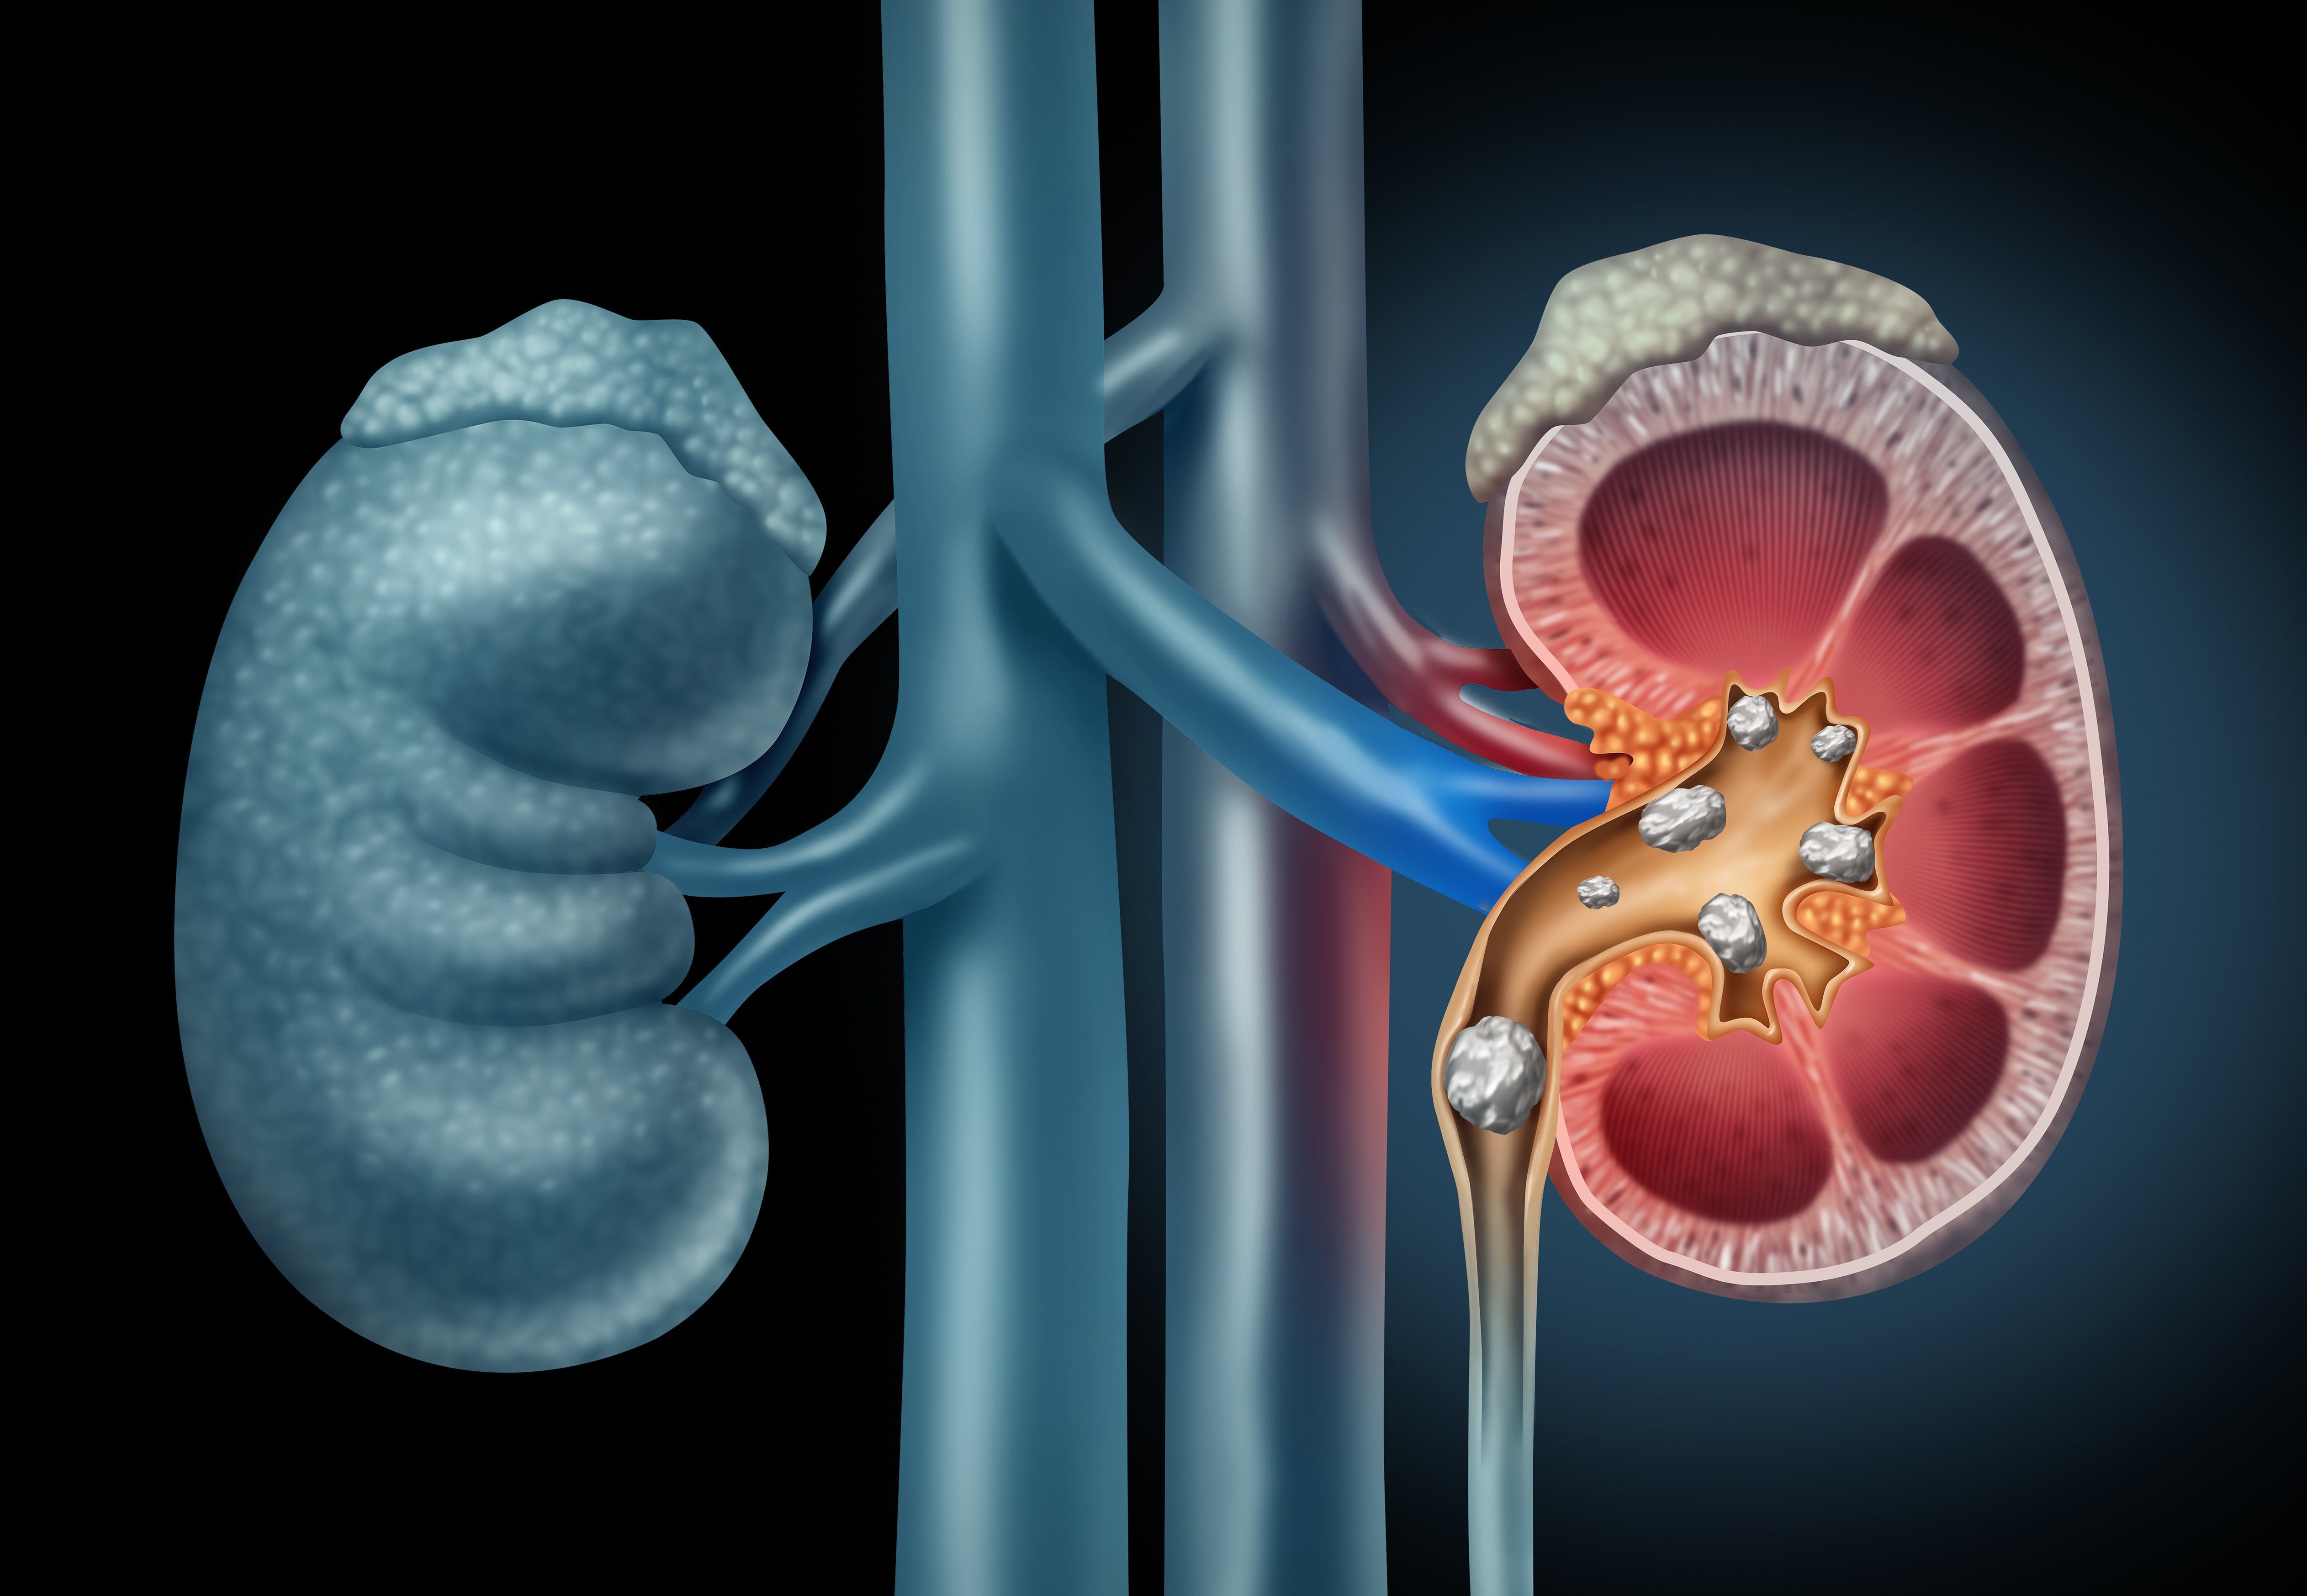

By the time a patient is diagnosed with SLE, nephritis has already set in for 35 percent of patients. The American College of Rheumatology offers screening, treatment and management guidelines for lupus nephritis patients. In this slideshow, we review the options.

Renal transplant can substantially improve survival rates for patients with lupus nephritis, according to new research.

There’s a higher risk of total organ damage and end-stage renal disease in patients with SLE.

The first step in reducing the burden of infection during lupus nephritis is understanding where and how it happens.